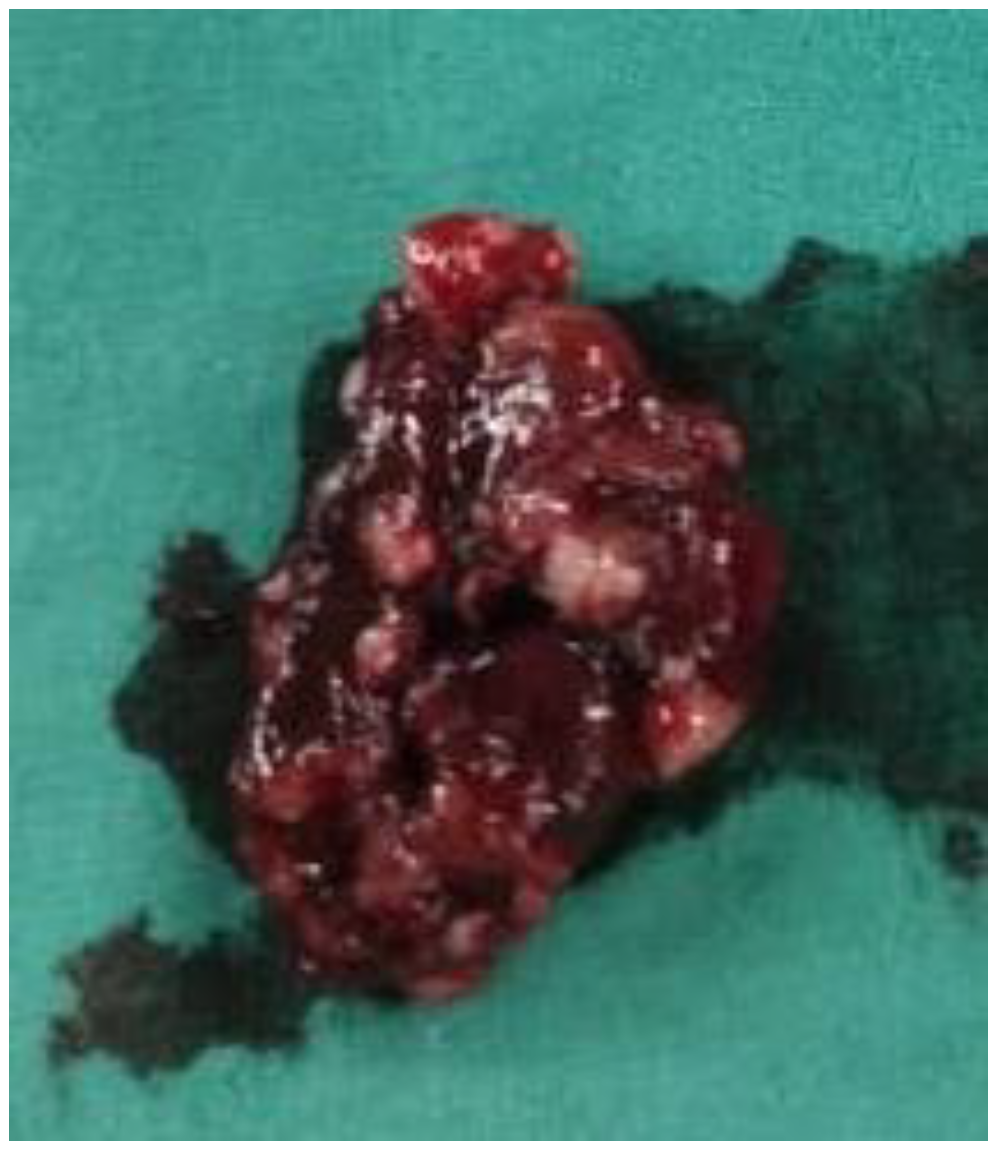

- ✓ Cistoscopia